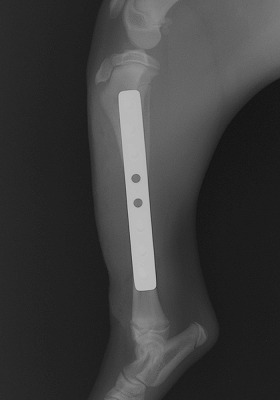

手術をして元の状態に骨を整復しました。

Img5980-1.jpg

手術後の経過もとてもよく元気も、元に戻りましたが、家の中で遊ぶのも気をつけましょう!